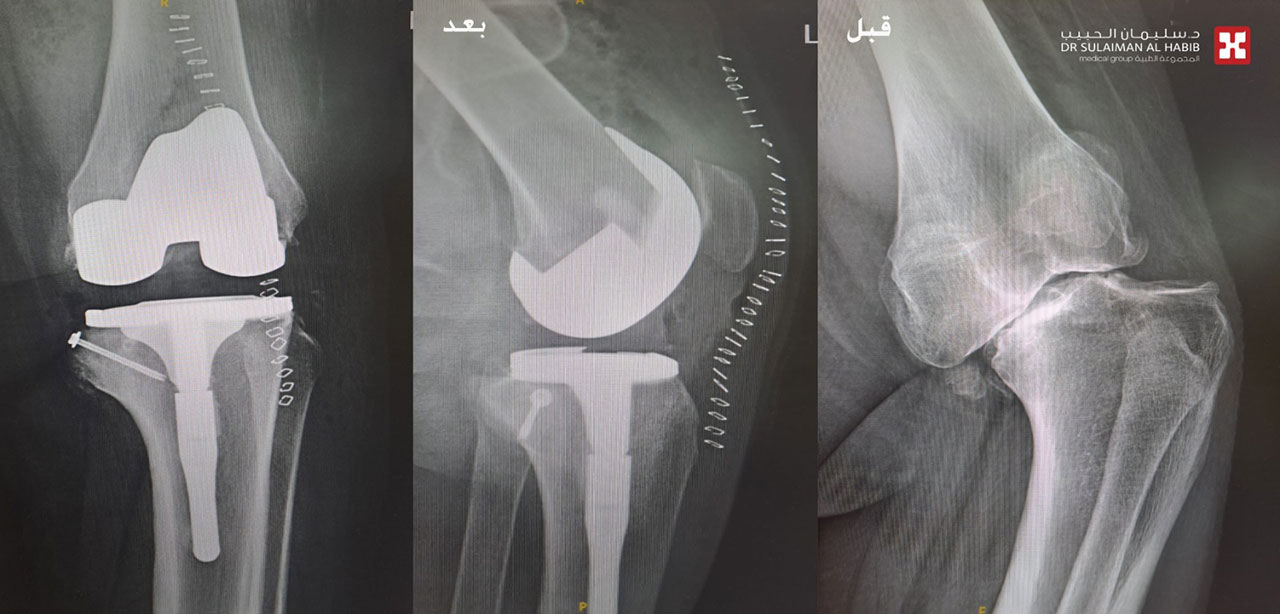

وأوضح الدكتور لؤي الخطيب استشاري جراحة العظام والمفاصل والإصابات الرياضية، رئيس الفريق الطبي المعالج، الحاصل على الزمالة البريطانية والكندية، أنه فور وصول المريض للمستشفى والاستماع إلى شكواه، والاطلاع على تاريخه المرضي، تبين أنه حاول العلاج مسبقاً في أكثر من مستشفى، ولكن دون جدوى، ودائماً ما كانت حالته تُرفض من قبل الأطباء، نتيجة التعقيد بعظام الركبتين لديه، مفيداً بأنه تم إخضاع المريض لحزمة من الفحوصات الطبية بالأشعة الرقمية «Digital X-rays»، والتصوير المقطعي «C.T Scan»، وكشفت النتائج عن وجود خشونة شديدة من الدرجة الرابعة بكلتا الركبتين، وإصابته بتشوه خلقي نادر يعرف باسم «Blount Disease»، وهو المتسبب في الأعراض التي عانى منها منذ الصغر.

وأشار الدكتور لؤي الخطيب إلى أنه بعد تجهيز المريض، أجريت له عمليتان جراحيتان، تم فيهما استبدال مفصلي الركبة، وتعديل وإصلاح التقوسات لكلتا الساقين، وقد تكللت جهود الفريق الطبي بالنجاح، بدون أية مضاعفات، نقل بعدها إلى جناح التنويم، وبدأ في برنامج علاج طبيعي تأهيلي مكثف، موضحاً أن المريض تلقى رعاية طبية فائقة على مدار الـ 5 أيام، واستعاد استقامة الساقين، وأصبح يمشي بصورة طبيعية، وقد خرج من المستشفى معافى.